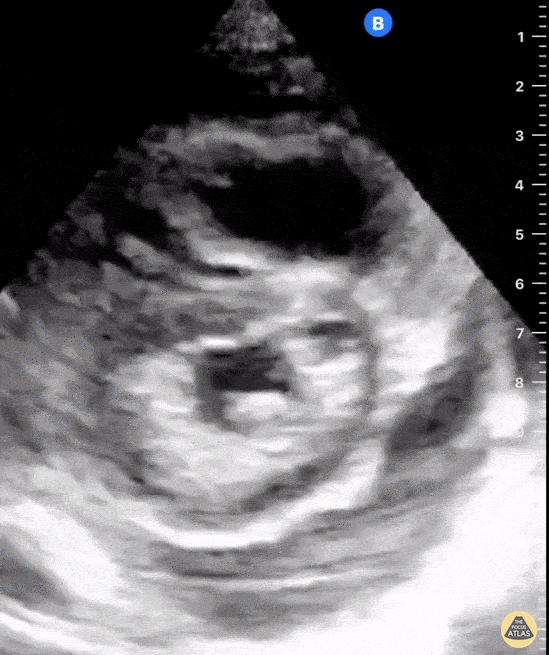

A 39-year-old female with known metastatic lung cancer complicated by multiple pulmonary emboli on apixaban presented with worsening dyspnea and productive cough over one week duration. POCUS identified a large circumferential pericardial effusion in multiple cardiac views in addition to signs of RV strain as demonstrated by flattening of her interventricular septum and ventricular interdependence (shown here on parasternal short axis view). The findings of RV strain are likely chronic and secondary to chronic thromboembolic disease complicated by pulmonary hypertension. Shahad Al Chalaby, MD. PGY3 Internal Medicine.Highland Hospital. Alameda Health System Residency Program. Oakland, CA, USA. @shahad_Chalaby Adam Mortimer, DO. PGY1 Internal Medicine. Highland Hospital. Alameda Health System Residency Program. Oakland, CA USA.